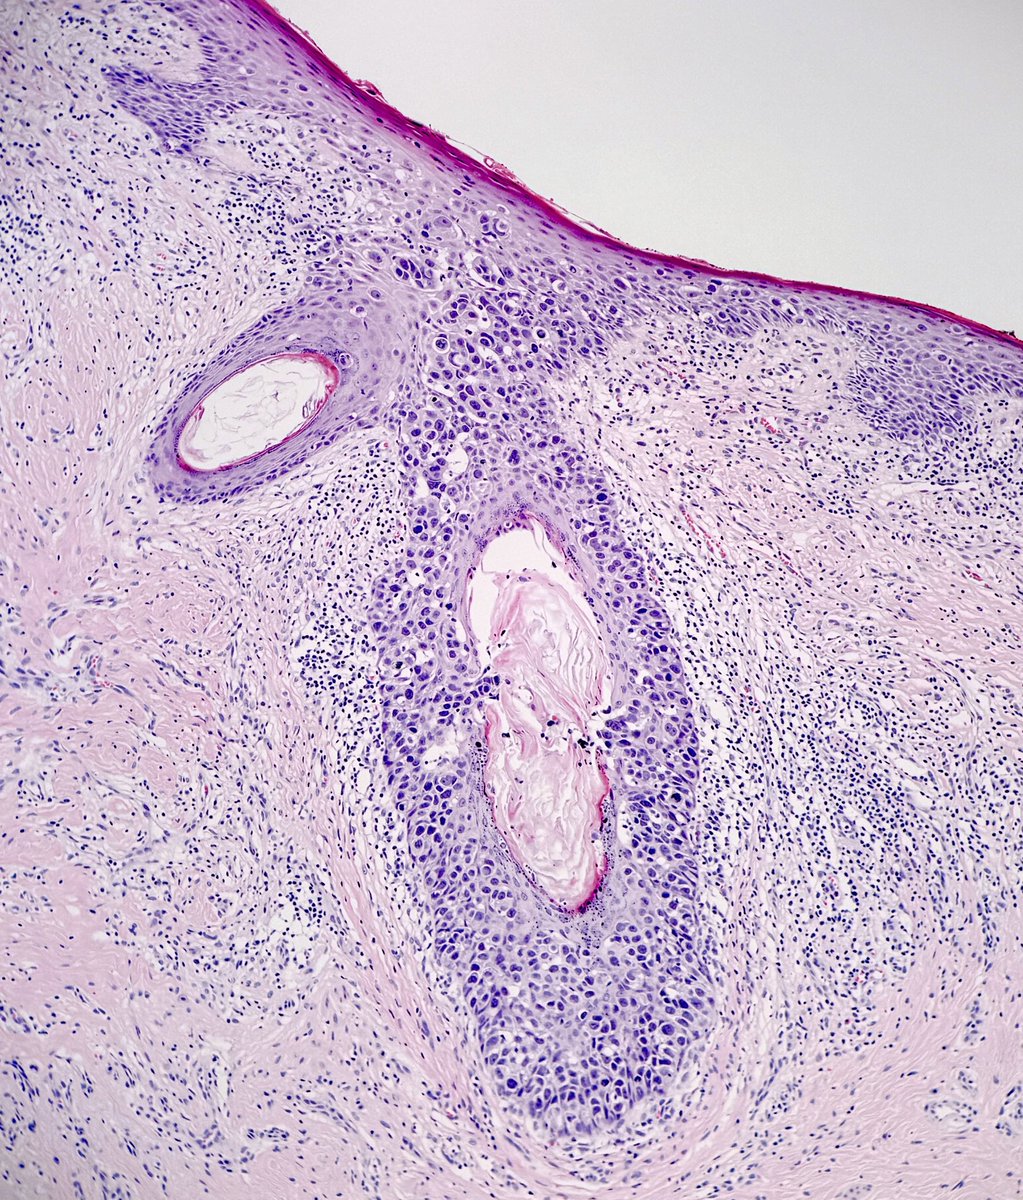

A beautiful example of the sine qua non for diagnosis of central centrifugal scarring #alopecia. Premature desquamation of the inner root sheath (in the s/c fat here). Rupture too. May be focal so keep those ๐Ÿ‘€ open๐Ÿ˜‰ #pathology #dermatology ๐Ÿ’™

A beautiful example of the sine qua non for diagnosis of central centrifugal scarring #alopecia. Premature desquamation of the inner root sheath (in the s/c fat here). Rupture too. May be focal so keep those ๐Ÿ‘€ open๐Ÿ˜‰